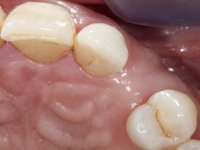

Female patient, 43 years old, non-smoker. Showed an edentulous space in the upper right canine area, resulting from tooth 1.3 impaction. The space had a mesio-distal diameter reduced to the normal size of the upper canine. This is consistent with the presence in the arch of the deciduous canine up to two years ago). Orthopantomography allows clearly view of tooth 1.3 impaction.The patient has a thick gingival phenotype and tolerable oral hygiene.

To define the dental zone to be covered by the Maryland bridge retainers, the patient was asked to perform maximum intercuspidation movements, and the contact points were marked with articular paper. Tooth preparation of the interproximal surfaces was made, to create a prosthetic insertion axis. It was sought that the mesio-distal diameter at the incisal level was equal to the diameter mesio-distal at the cervical level, that is to say, the interproximal walls were parallelized. Tooth preparation was done with fine grain diamond drills, and later polishing was done with abrasive discs. Color information was collected even before confection of the impression, to avoid dehydration of the arcade. Definitive impression was made using wash technique impression with silicone of heavy and regular consistency, both with fast setting, and a working plaster model was prepared in the lab. A laboratory scanner was used to scan the working model, and later, the infrastructure for the Maryland bridge was made using a CAD-CAM process. Ceramic was placed on this subframe. A ceramic adhesive was applied to the internal surface of the wings and connectors, which would enable bonding to the adjacent teeth. The adhesive bridge was bonded in the mouth following the conventional bonding technique. After bonding, the protrusion and laterality movements were carefully checked to avoid undesirable contacts.